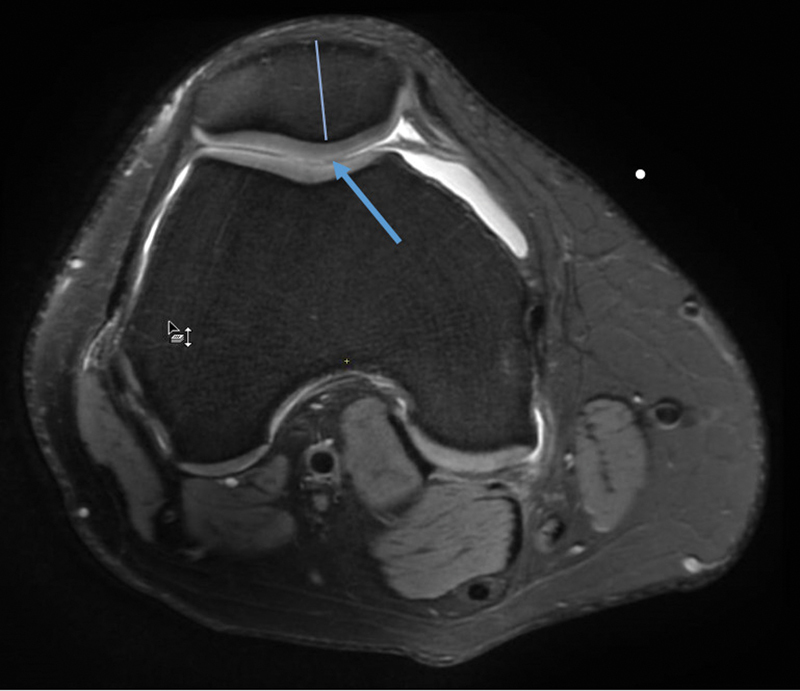

Background  Knee joint osteoarthritis (OA) is among the most prevalent degenerative diseases of the joints in the body. Various scoring system exists for grading OA, such as (1) magnetic resonance imaging (MRI) Osteoarthritis Knee Score (MOAKS), (2) clinical grading by Western Ontario and McMaster Universities Arthritis Index (WOMAC), and (3) X-ray grading of the Kellgren-Lawrence grading system (K-L). Objectives  To study MRI findings and MOAKS scoring of knee OA and correlation with WOMAC and K-L scoring. Setting and Design  Cross-sectional study in hospital population. Materials and Methods  A total 40 knee OA cases underwent an MRI of the knee. MOAKS scoring was done and compared with K-L grading and WOMAC scores. Statistical Analysis  Collected data were compiled systematically and interpreted using IBM SPSS statistics software 25.0. A p -value of less than 0.05 was considered significant. Results  The mean total WOMAC score was 9. K-L grade 2 was the most prevalent X-ray grade. Bone marrow lesion (BML) and cartilage loss in MOAKS score were greater in the medial femorotibial region. A moderate positive correlation was noted between the WOMAC score and K-L grade; full-thickness articular cartilage loss score at the medial femorotibial joint (MFTJ) and WOMAC score; partial-thickness articular cartilage loss score at lateral femorotibial joint (LFTJ) and WOMAC total pain score. No correlation was found between BML and pain severity score. Conclusion Higher WOMAC scores were associated with higher grades of K-L scoring and score of cartilage loss (partial and full thickness) of the MOAKS scoring system. The rest of the features of the MOAKS score (BML score, osteophyte, and synovitis) had no significant association with pain severity and K-L grading.

Abstract Image